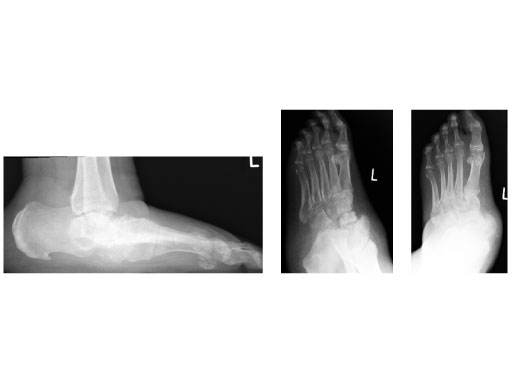

A 64-year-old man presented with severe ankle and subtalar arthritis accompanied by large cysts in the talus and calcaneus. Eighteen months after hindfoot fusion with the HAN he walked without pain.

Case provided by Stefan Rammelt, Dresden, Germany